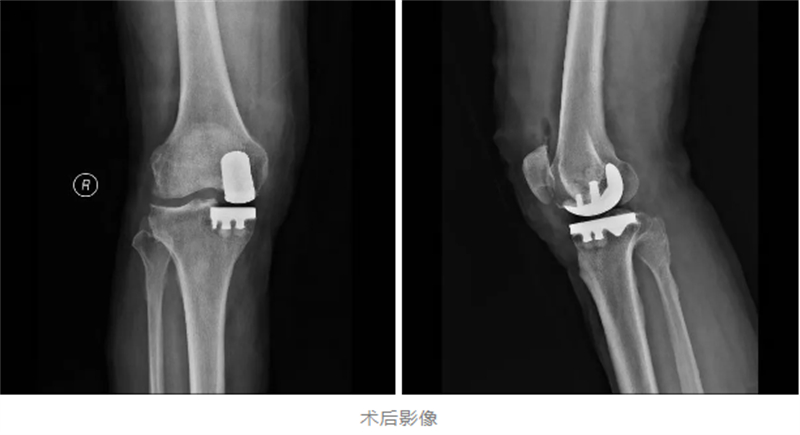

為確保手術(shù)安全與術(shù)后快速康復(fù),關(guān)節(jié)骨病科與麻醉科展開深度協(xié)作,精心制定了個(gè)性化的麻醉方案和手術(shù)計(jì)劃。手術(shù)中,采用了“超聲引導(dǎo)下區(qū)域神經(jīng)阻滯”加“全麻”的方式,既確保了手術(shù)過程中的無痛和舒適,又減少了麻醉對患者的副作用。手術(shù)當(dāng)天,多學(xué)科團(tuán)隊(duì)配合默契,僅用1小時(shí)便順利完成了置換手術(shù)。

患者麻醉蘇醒后身體狀態(tài)良好,既無頭暈惡心等不適反應(yīng),下肢肌力也保持正常,手術(shù)切口痛感輕微。令人欣喜的是,在醫(yī)護(hù)人員的全程保障下,患者術(shù)后就能下地行走,自行走出手術(shù)室,借助助行器穩(wěn)穩(wěn)地返回了病房。